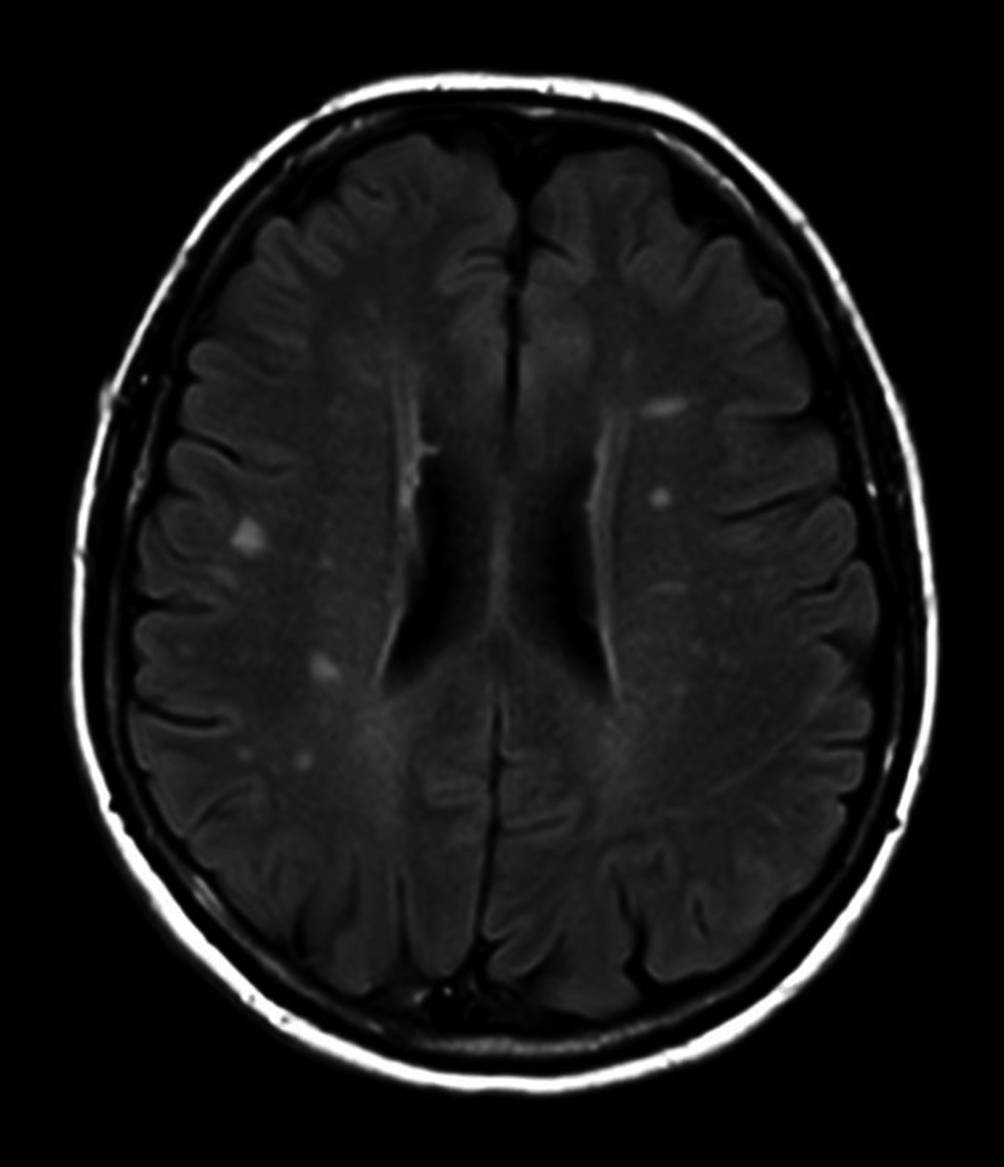

Abb. 6

Zerebrale Magnetresonanztomographie (MRT) (T2W FLAIR) mit multiplen hyperintensen Läsionen bei multipler Sklerose

Die multiple Sklerose (MS) ist eine chronisch entzündliche Erkrankung des zentralen Nervensystems (ZNS). Sie ist durch Entzündungen, Demyelinisierung, Gliose und neuroaxonale Degeneration gekennzeichnet und betrifft überwiegend junge Frauen (Abb. 6; [14]). Die Diagnose wird anhand der McDonald-Diagnosekriterien aus klinischen, radiologischen und Laborergebnissen gestellt [15]. Während die Augenbeteiligungen in Form der Optikusneuritis oft mit der MS in Verbindung gebracht werden, ist dies bei der Uveitis seltener der Fall. Bei Patienten mit MS sind die intermediäre Uveitis und retinale Vaskulitis in Form der Phlebitis die häufigste Manifestation. Sie kann asymptomatisch verlaufen und ist in der FAG zu diagnostizieren. Als wichtige Komplikationen sind das zystoide Makulaödem, die Bildung epiretinaler Membranen und eine okklusive Vaskulitis zu nennen.